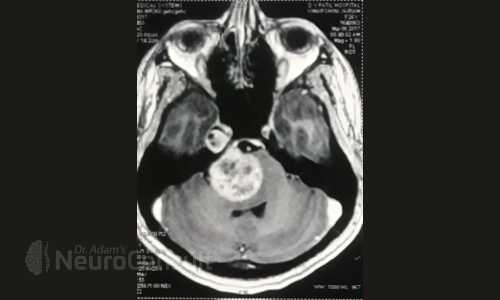

My Cases Studies & Work